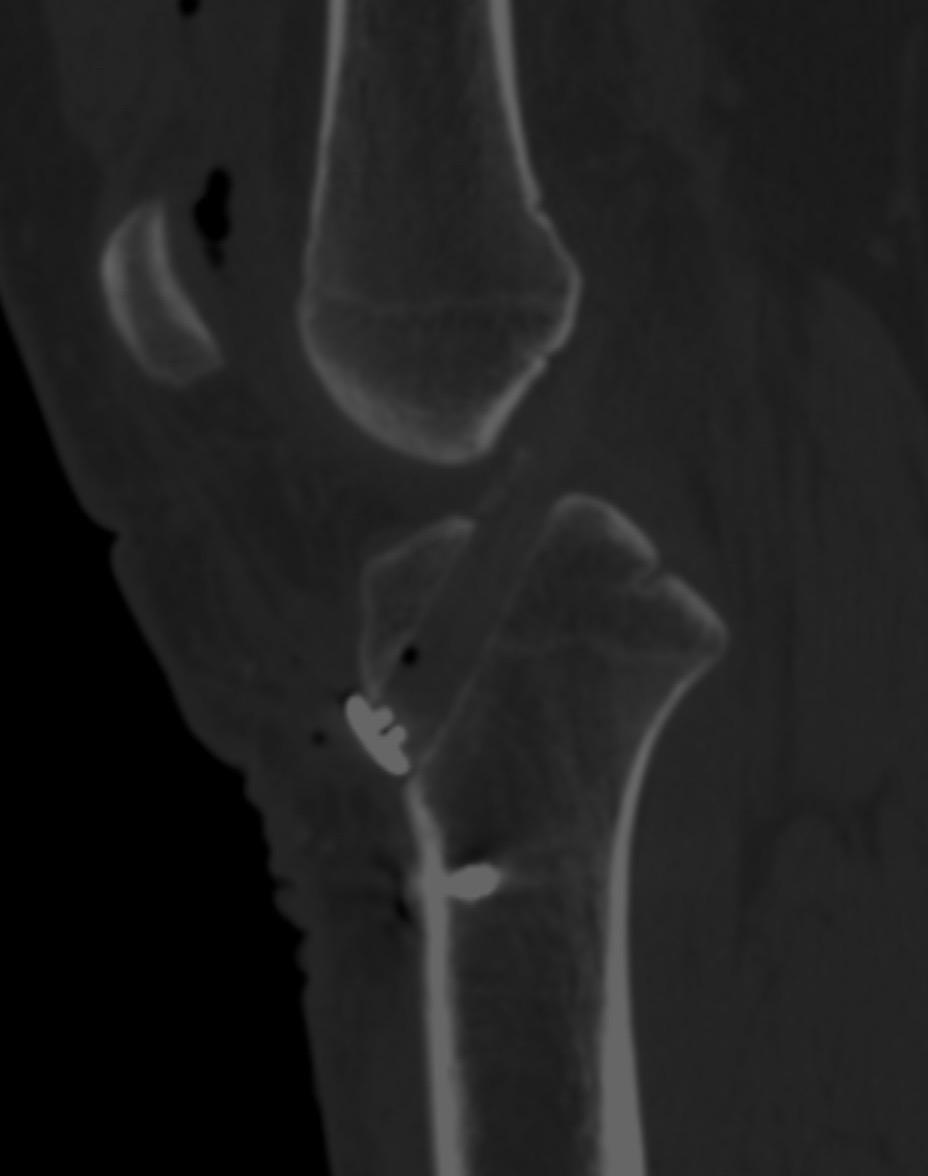

前交叉韧带重建。每一张图片,都是对细节的苛求;每一次重建,都是对精准的不懈探索。